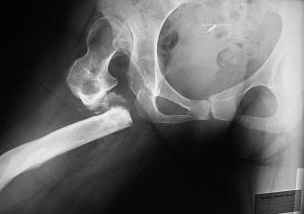

Bolnjia 30 let, stradaet ot vrozdennogo vyviha bedra, hodila i zila sebe spokoino, poka ne nashelsya hirurg, kotory pytalsa uluchit' eezhizn' i pohodku i v rezultate poluchilas', kak Vi vudete.

KAK MOZHNO EI POMOCH"????????????????Ei bilo predlozeno THR! No , ---- est' mogo no, est' bolee realnoe reshenjie??? Spasibo Zaranee vsem uchastnikamYours Dr. Castro